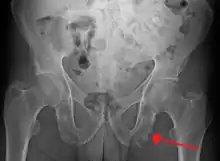

Enthesopathy of the pelvis likely due to ankylosing spondylitis